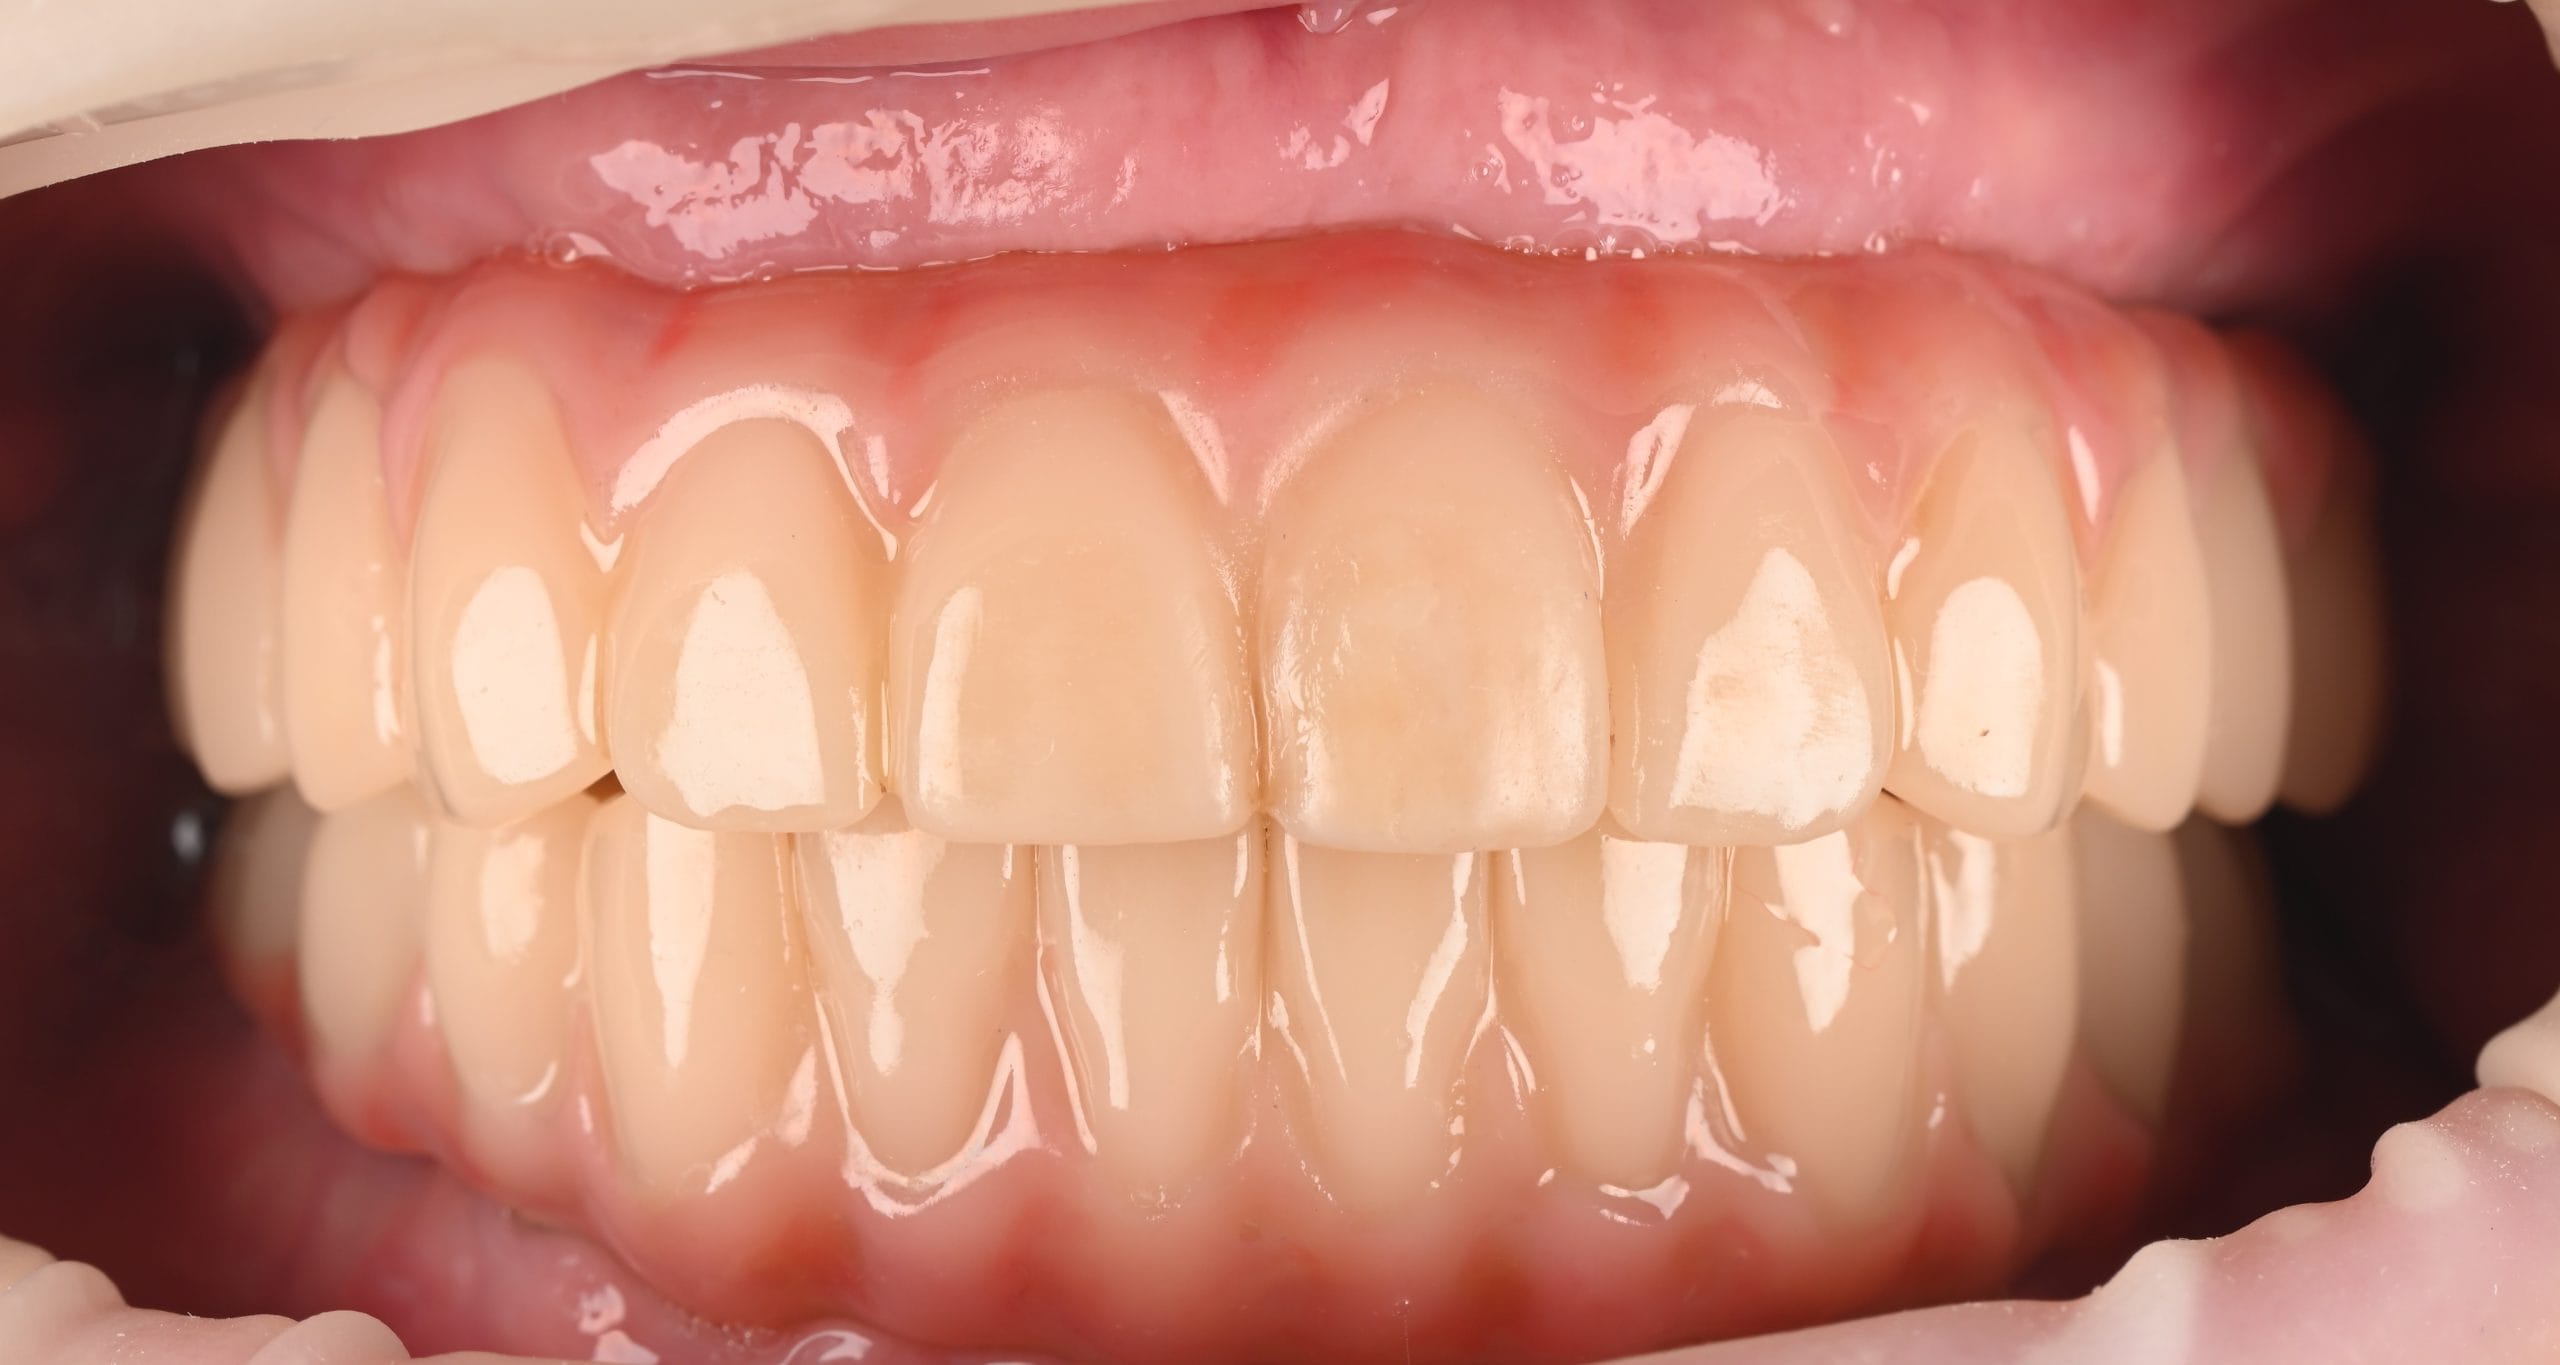

Lucrarea finală este realizată individual, în funcție de forma feței și de zâmbet, cu materiale biocompatibile și aspect natural.

Redarea funcției masticatorii și estetice prin restaurări complexe cu ajutorul coroanelor pe implanturi tip FP1, cu aspect natural si sănătos al gingiei.

Dantura fixă arată natural?

Da. Lucrarea finală este realizată personalizat pentru fiecare pacient, cu materiale ceramice sau compozite care reproduc perfect aspectul natural al dinților.